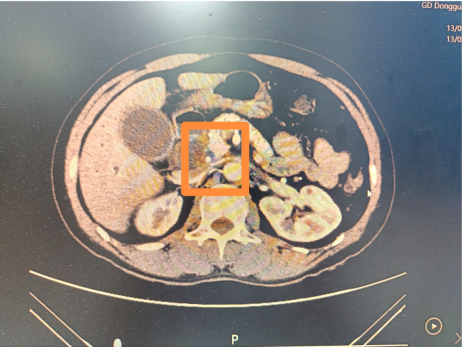

普通外科霍胜军主任检查发现,黄大叔的胆总管下段卡着一颗8毫米的结石,几乎完全堵塞管道。

胆总管结石位置

传统手术需切开胆总管取石并留置T管4-6周,患者需忍受管道护理难、感染风险高、行动不便等问题。